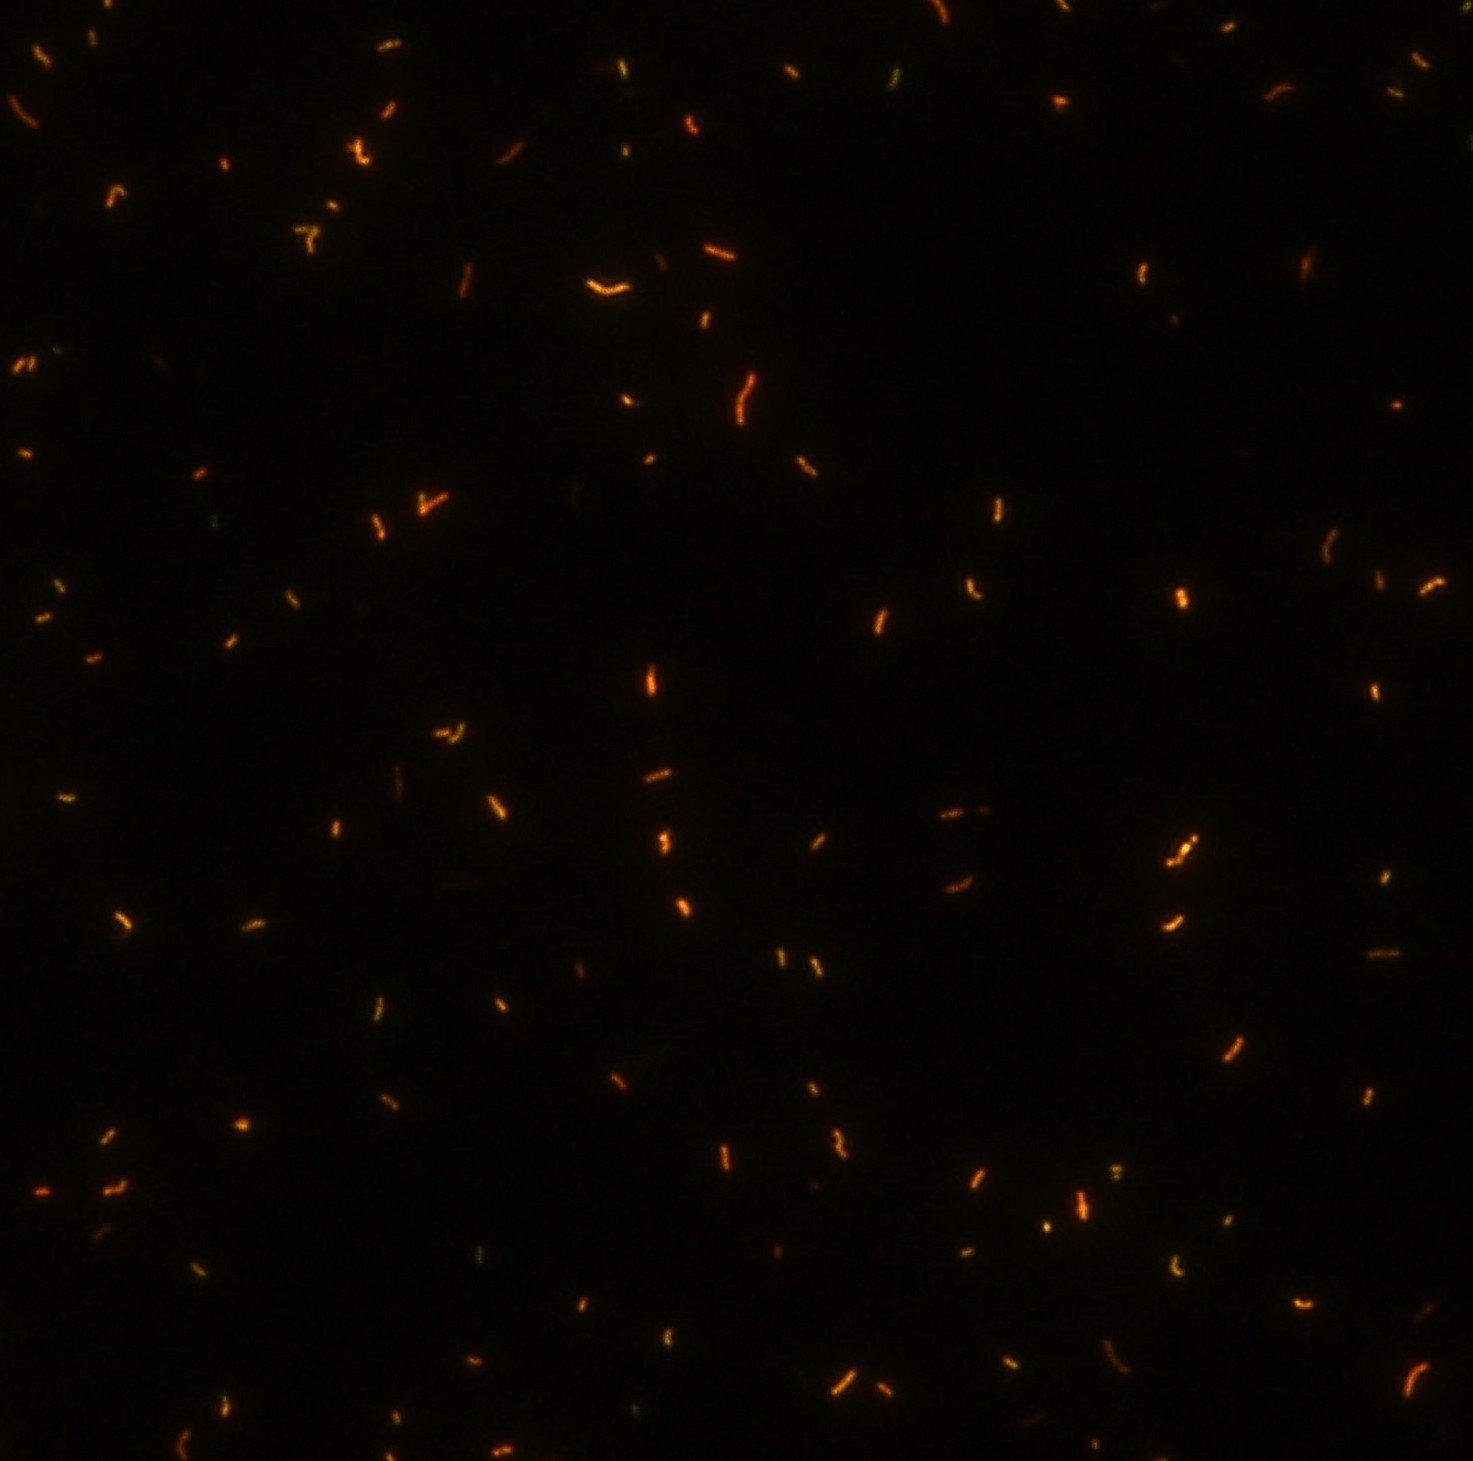

顯微染色技術(shù)是檢測(cè)結(jié)核桿菌方法之一。分枝桿菌細(xì)胞壁中含有分枝菌酸,其可以與染料牢固結(jié)合,具有“抗酸性”的特征。熒光染料金胺-羅丹明在染色中與抗酸生物細(xì)胞壁內(nèi)的分枝菌酸相結(jié)合,并耐受酸醇(脫色劑)清洗脫色。反染色劑高錳酸鉀被用來顯出染色生物。AFB(熒光)染色試劑盒設(shè)計(jì)既可用于自動(dòng)染色機(jī),也可用于手工染色。產(chǎn)品穩(wěn)定性好,染色效果佳。

染色結(jié)果 (熒光法×400)

用于分枝桿菌、諾卡菌等細(xì)菌抗酸染色,包括熒光染色。